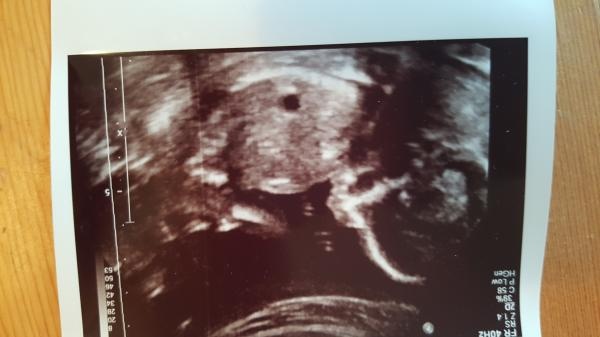

RUL idag! En vild liten sprattelpojk låg och gjorde volter! Moderkaka i framvägg, därav inga supertydliga knuffar och puffar än. Allt såg bra ut och jag går på moln! Flyttad från 1 november till 29 oktober, alltså 18+4 idag. Mys <3

• Lilla Luna

Blev flyttad från 28 okt till 9 nov igår på rul. Bråkstaken i magen var liten och ville inte all samarbeta så vi ska in igen 21a. Men 9 nov betyder äl 4-5 dagar innan jag testade positivt. Känns som ett missvisande datum, men men. Bebis kommer ju när bebis är redo. Jag vill och hoppas på att det blir tidigare och att det blir i oktober. Har så många som fyller år i början på november redan.

Bilden vägrar bli åt rätt håll...